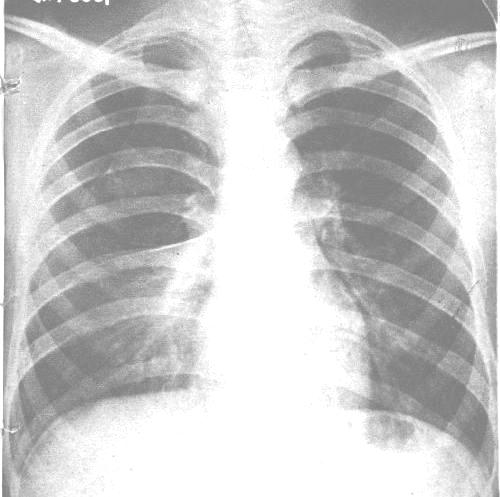

自发性气胸根据造成气体溢入胸膜腔的原因分为:特发性气胸和继发性气胸。特发性气胸多见于青少年,体形瘦高,在X线胸片上甚至在开胸手术直视下,在脏层胸膜表面往往见不到明确的病灶。继发性气胸在中老年人多见,往往由于肺内原有的病灶破裂所致,如肺大疱、肺结核、肺脓肿、肺癌等。气胸病人的临床症状和体征取决于基础病因、肺萎陷的程度以及是否存在基础肺部疾病。

1.胸膜下肺大疱破裂 青少年自发性气胸多因肺尖部胸膜下的肺大疱破裂所致。胸膜下肺大疱大多分为两类,胸膜下微小肺大疱(bleb),直径<1cm,常为多发,可发生于肺尖部、叶间裂边缘及肺下叶边缘。这类微小肺大疱往往是支气管和肺部炎症愈合、纤维组织瘢痕形成过程中牵拉及通气不畅所致。胸膜下微小肺大疱所致的自发性气胸在X线胸片上或手术时不易发现病灶,故亦称为“特发性气胸”。胸膜下肺大疱常为单发,多发生于肺尖部,由于脏层胸膜先天性发育不全,逐渐出现肺大疱,这类自发性气胸常见于瘦高体形的青少年,在手术过程中,除发现肺大疱外,常不能找到与之相关的肺实质内的基础病变。这两类肺大疱破裂引起的自发性气胸可在剧烈活动、咳嗽、喷嚏后诱发,亦可在安静状态下发生。

2.大泡性肺气肿破裂 由于慢性阻塞性肺部疾患使肺泡单位过度充气,久之出现肺泡壁破坏,即小叶中心型肺气肿和全小叶型肺气肿,肺泡进一步融合压迫肺泡间隔和肺间质形成大泡性肺气肿,其特点是在X线胸片和胸部CT片上可见到大泡内有被压的极薄的血管和肺泡间隔,以此与巨大肺大疱鉴别。当肺实质内残气量进一步增加,压力过高引起脏层胸膜破裂就出现气胸。40岁以上的男性多见,常伴有慢性咳嗽、长期吸烟史、支气管哮喘史等。